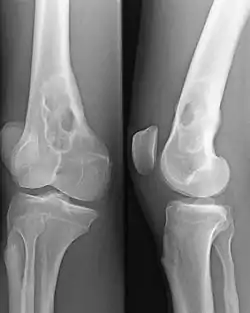

La radiographie du squelette montre très fréquemment des lésions osseuses de type ostéolyse.

La tomodensitométrie à faible dose de tous le corps est plus sensible que la radiographie conventionnelle pour décrire les aspects ostéolytiques ; elle est recommandée depuis 2015 en Europe comme nouvelle norme pour détecter les lésions lytiques du grade 1A du myélome[38].